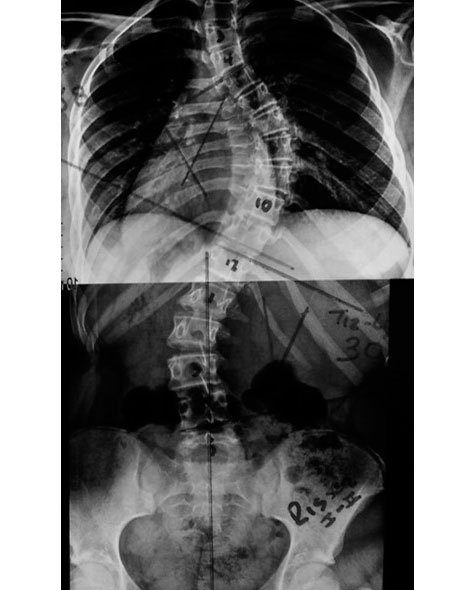

¿Como determinar el potencial de crecimiento oseo?

El mas usado es el signo de risser que nos permite evaluar la aparición del nucleo de osificación en la cresta iliaca

¿Aumentara mi Escoliosis?

Dos factores son los mas importantes para predecir la progresión: